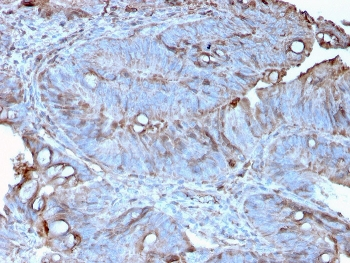

IHC staining of FFPE human colon carcinoma with MerTK antibody (clone TPKR-1). HIER: boil tissue sections in pH9 10mM Tris with 1mM EDTA for 10-20 min and allow to cool before testing.